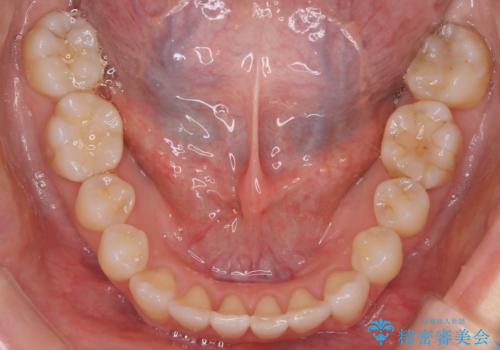

八重歯と前歯のガタガタをインビザラインで

インビザラインで目立たずに治療を終えることができ、喜んでいただけました。